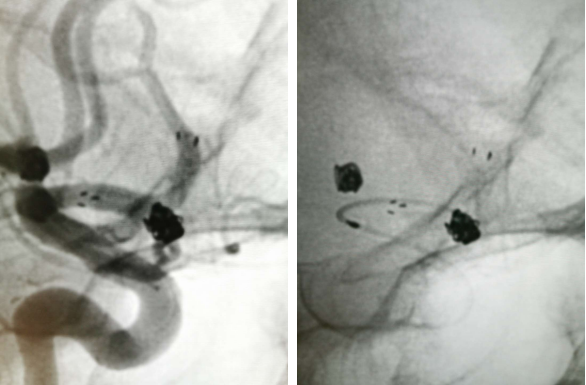

经右侧股动脉鞘,黑泥鳅导丝带领导引导管(Codman 6F Envoy DA)到达右侧颈内动脉岩段,微导丝(Synchro--14 0.014 in*200 cm)带领支架微导管(Excelsior SL--10)到达右侧大脑中动脉M2段,退出微导丝。微导丝带领弹簧圈微导管(Echelon10)到达右侧M1远端分叉处动脉瘤内,退出微导丝。经弹簧圈微导管填入弹簧圈(Codman 3 mm*4 cm)经支架微导管输送支架(Neuroform Atlas 3.0 mm*15 mm)并释放在M2段至M段中部,完全覆盖动脉瘤颈。继续经弹簧圈微导管依次填入弹簧圈数枚,间断造影确保右侧大脑中动脉及远端血流通畅。右侧颈内动脉造影确认:动脉瘤致密填塞,载瘤动脉通畅,手术结束。有侧股动脉穿刺处用血管封堵器封堵,并压迫器持续压迫。术后患者麻醉清醒,拔除气管插管,呼唤应答,对答切题,言语清楚,四肢肌力肌张力正常。安返病房。

患者在全麻下、多参数监护仪监测下行前交通动脉瘤经右侧颈内动脉支架辅助下栓塞术。全麻后,常规消毒销巾,采用改良seldinger技术穿刺右侧股动脉或功,置入6F动脉鞘。黑泥鳅导丝及多功能导管带领6F MPD导管达到右侧颈内动脉岩段,行造影见∶前交通动脉瘤,瘤体3.5 mm*5.1 mm。在路图引导下,徵导丝(Synchro 0.014 in*200 cm)带领弹支架微导管(SL-10)到右侧大脑前动脉A2段,退出微导丝。微导丝(Synchro 0.014 in*200 cm)带领弹簧圈微导管(eV3 Echelon-10)到达前交通动脉瘤体内,退出微导丝。经弹簧圈微导管填入首枚弹簧圈(Codman COMPLEX XTRASOFT3 mm*6 cm)成篮良好,在路图引导下在支架管内输送支架(Neuroform Atlas 3.0 mm*21 mm)并释放完全覆盖动脉瘤颈,造影可见支架打开良好解脱首枚弹备圈,沿弹簧圈导管继续填入弹簧圈(可见护理记录单)间断造影确保双侧大脑前动脉血流通畅。右侧颈内动脉造影确认∶前交通动脉瘤填塞致密,双侧大应前动脉血流通畅。手术结束。右侧股动脉鞘处用血管封堵器(Coxrds Exoseal 6F)封堵,并压迫器持续压迫。木后患者清醒。

颅内动脉分叉处宽颈动脉瘤一直是介入治疗的一个难点,存在支架到位困难、介入栓塞术后复发率高的特点。大脑中动脉分叉部动脉瘤与前交通动脉瘤临床使用Neuroform Atlas新型支架,有望进一步提高支架到位与栓塞成功的比率。

Neuroform Atlas支架用于辅助弹簧栓塞治疗颅内宽颈动脉瘤,术后一年具有较高的动脉瘤闭塞率以及良好的安全性。有文献报道Atals支架能有效提高动脉瘤的闭塞率从术后即刻到术后一年由60%提升至86.7%。